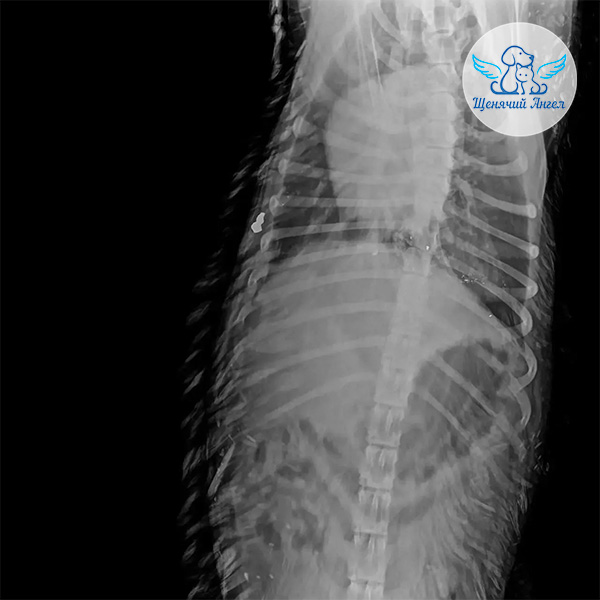

По прибытии в клинику Нео сразу прошёл полное обследование: его осмотрел хирург, был выполнен рентген и взяты необходимые анализы на инфекции ⚕️

По результатам диагностики в области рёбер с обеих сторон обнаружены входные отверстия от пуль без образования полостей, с небольшими кровянистыми выделениями.

🩻 Рентген показал, что одна из пуль остаётся в теле – она расположена под кожей справа. Жизненно важные внутренние органы не задеты 🙏🏻